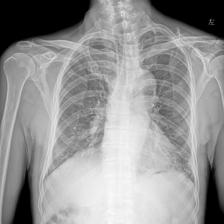

To pre-train a high-performance X-ray foundation model, the first thing we need to do is the collection of large-scale X-ray images. Therefore, a large-scale and high-resolution dataset that contains X-ray medical images is collected for the pre-training. Some representative samples are visualized in Fig. 3.